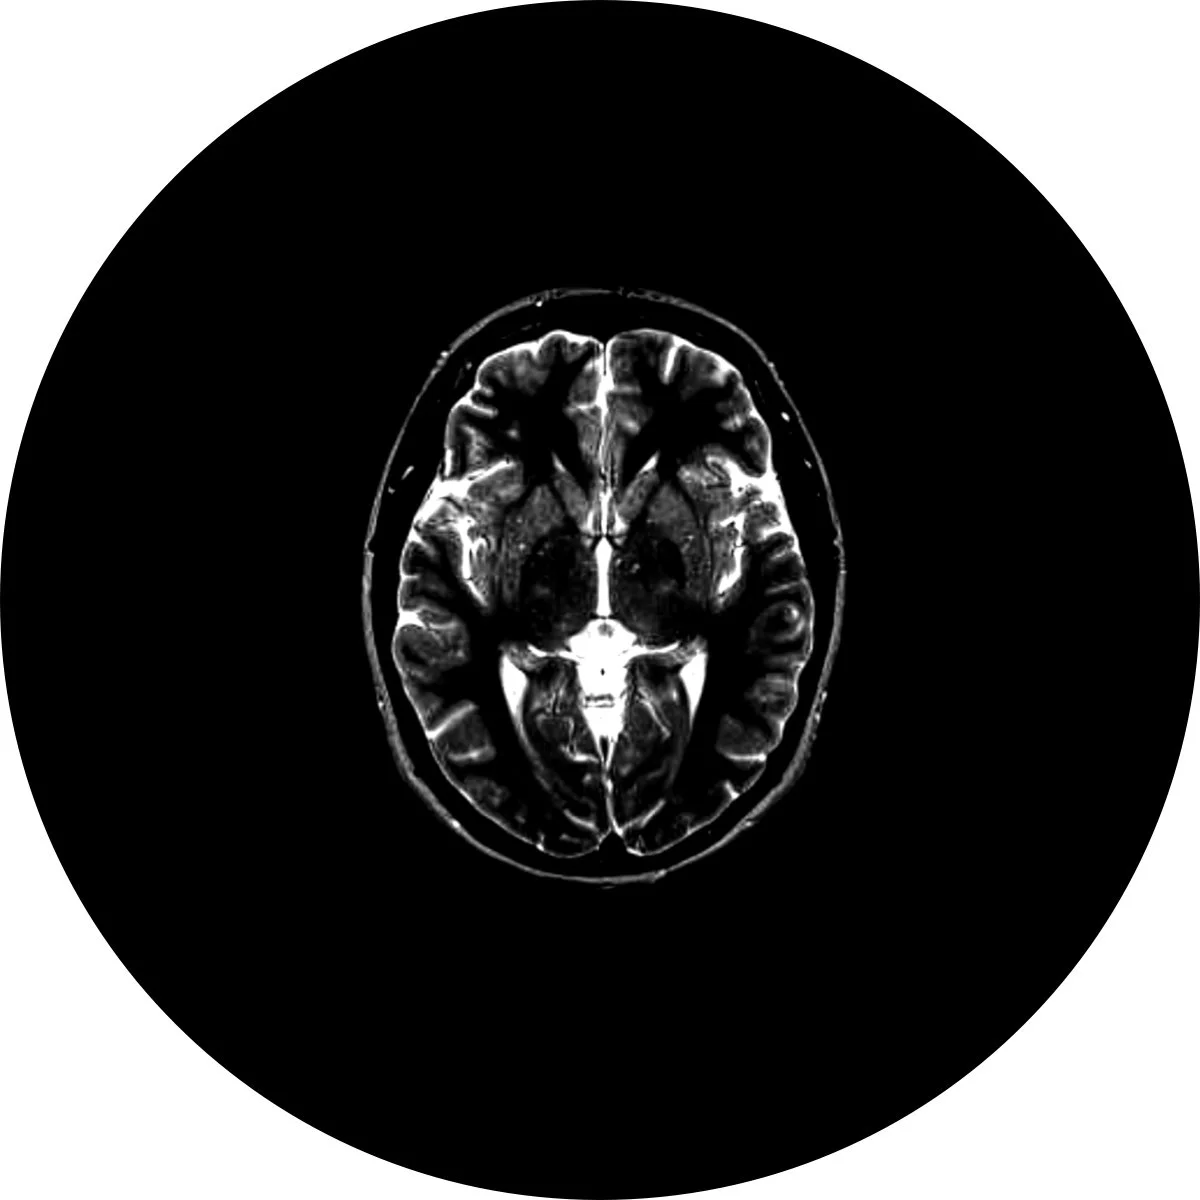

The Bionaut moves in a 3D trajectory and is free of the constraints of conventional surgical entry corridors and safe passageways.

MicrosurgicalReaching inaccessible regions in the brain

The micro-robot can access places in the brain currently extremely difficult or impossible to access; the Bionaut is removed from the body after each procedure